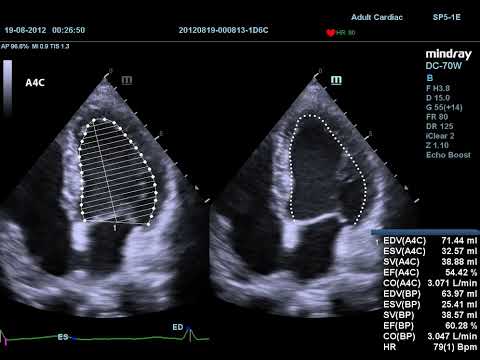

Auto EF

Auto EF - это интеллектуальный способ анализа изображений двухмерной эхокардиографии для автоматического распознавания диастолических и систолических кадров и вывода измерений для оценки функционирования таких параметров левого желудочка, как КДО, КСО и реакции выброса.

- Автоматическое распознавание А2C или А4С

- Автоматическое распознавание границы эндокарда

- Автоматическое распознавание диастолических и систолических значений